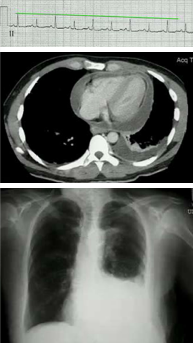

A 59 year old long-standing HIV patient presents with a CNS lesion. CD4 count is

Diffuse Large B Cell Immunoblastic Lymphomas are the most common cause of primary CNS lymphoma in patients with HIV. These are always EBV+ and have a poor prognosis. Tx with ARTs, radiation, high dose MTX w/leucovorin rescue, temozolomide and rituximab (Anti-CD20) followed by ARA-C with etoposide.

A 26 year old HIV patient presents with progressive dyspnea. RR 35, P 125, BP 103/60 w/pulsus paradoxus of 25 mmHg on inspiration. Labs show electrical alternans, pericardial/pleural effusions. Biopsy reveals B-cells that are LANA positive. What is causing his condition and how do you treat it?

Primary effusion lymphoma is caused by KSHV infection of B cells. There is never a solid mass, it is usually confined to the pericardium, pleura and peritoneal cavity. They are CD20 negative so rituximab won’t work and the tumor is refractory to chemotherapy so prognosis is very poor (